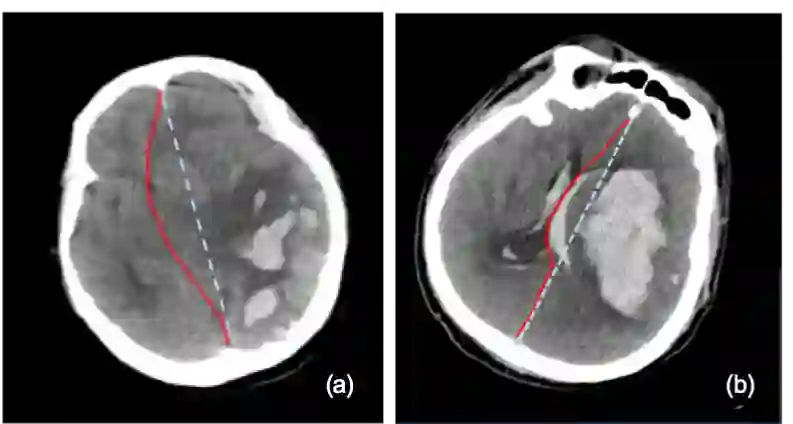

The midline related pathological image features are crucial for evaluating the severity of brain compression caused by stroke or traumatic brain injury (TBI). The automated midline delineation not only improves the assessment and clinical decision making for patients with stroke symptoms or head trauma but also reduces the time of diagnosis. Nevertheless, most of the previous methods model the midline by localizing the anatomical points, which are hard to detect or even missing in severe cases. In this paper, we formulate the brain midline delineation as a segmentation task and propose a three-stage framework. The proposed framework firstly aligns an input CT image into the standard space. Then, the aligned image is processed by a midline detection network (MD-Net) integrated with the CoordConv Layer and Cascade AtrousCconv Module to obtain the probability map. Finally, we formulate the optimal midline selection as a pathfinding problem to solve the problem of the discontinuity of midline delineation. Experimental results show that our proposed framework can achieve superior performance on one in-house dataset and one public dataset.